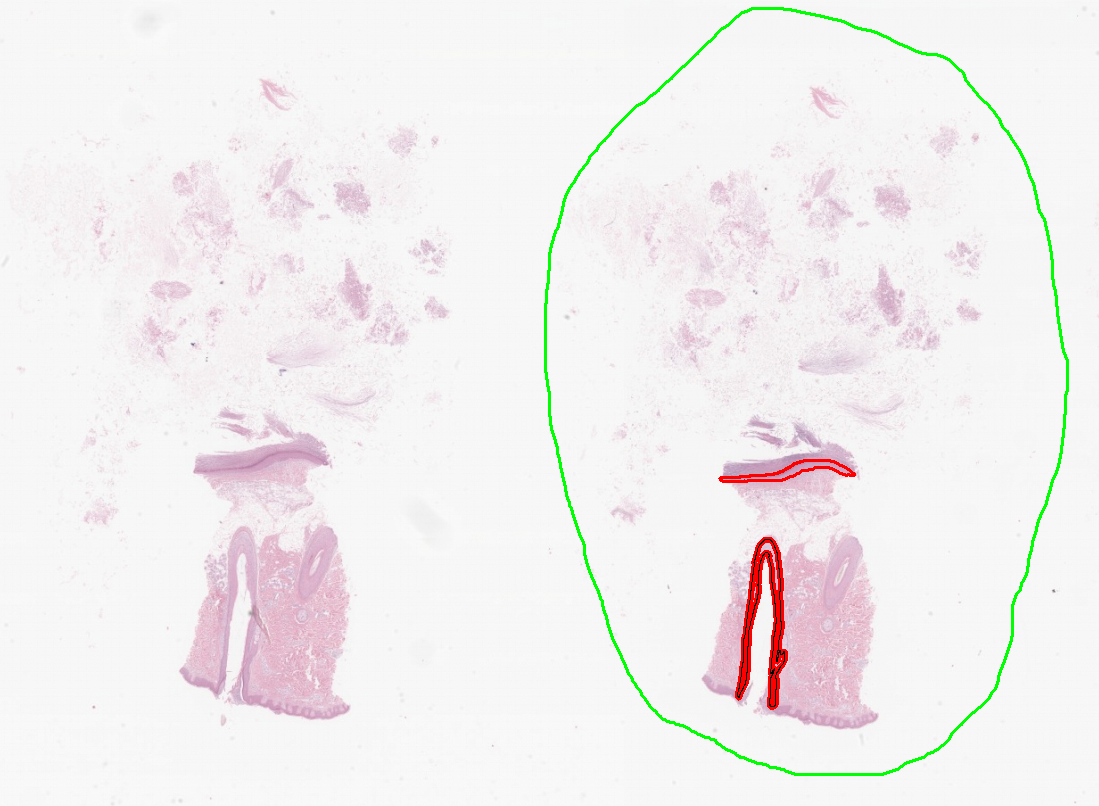

![[ 피부계 데이터 학습 모델 검증 예시 ]](/cms/images/ckimages/71519/ai_model_source_2.png)

1) 세부데이터별 원천데이터와 데이터 가공 예시

- 표피낭종 (Epidermal cyst)

- 지루각화증 (Seborrheic keratosis)

- 보웬병/편평상피암 (Bowen disease/Squamous cell carcinoma)

- 기저세포암 (Basal cell carcinoma)

- 멜라닌세포모반 (Melanocytic nevus)

- 흑색종 (Malignant melanoma)

- 정상피부조직 (Normal)